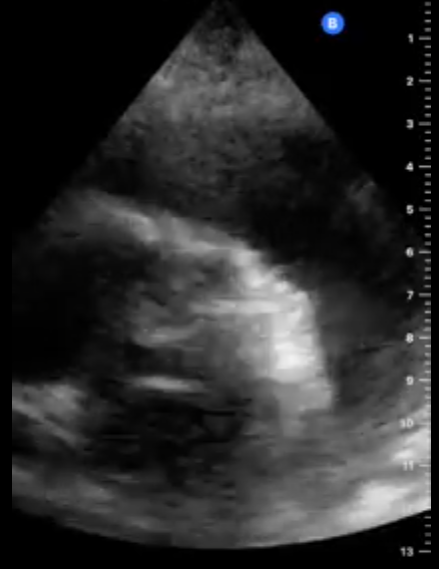

En la ecocardiografía se aprecia latido cardiaco con intercambio de flujos muy disminuido y el miocardio movilizándose en el interior del derrame pericárdico contenido sin taponamiento.

En este caso tenemos un cuadro de derrame pericárdico con repercusión hemodinámica pero apreciándose latido cardíaco y suficiente contractilidad como para no incurrir en taponamiento cardíaco que hubiera supuesto una emergencia vital para la paciente.